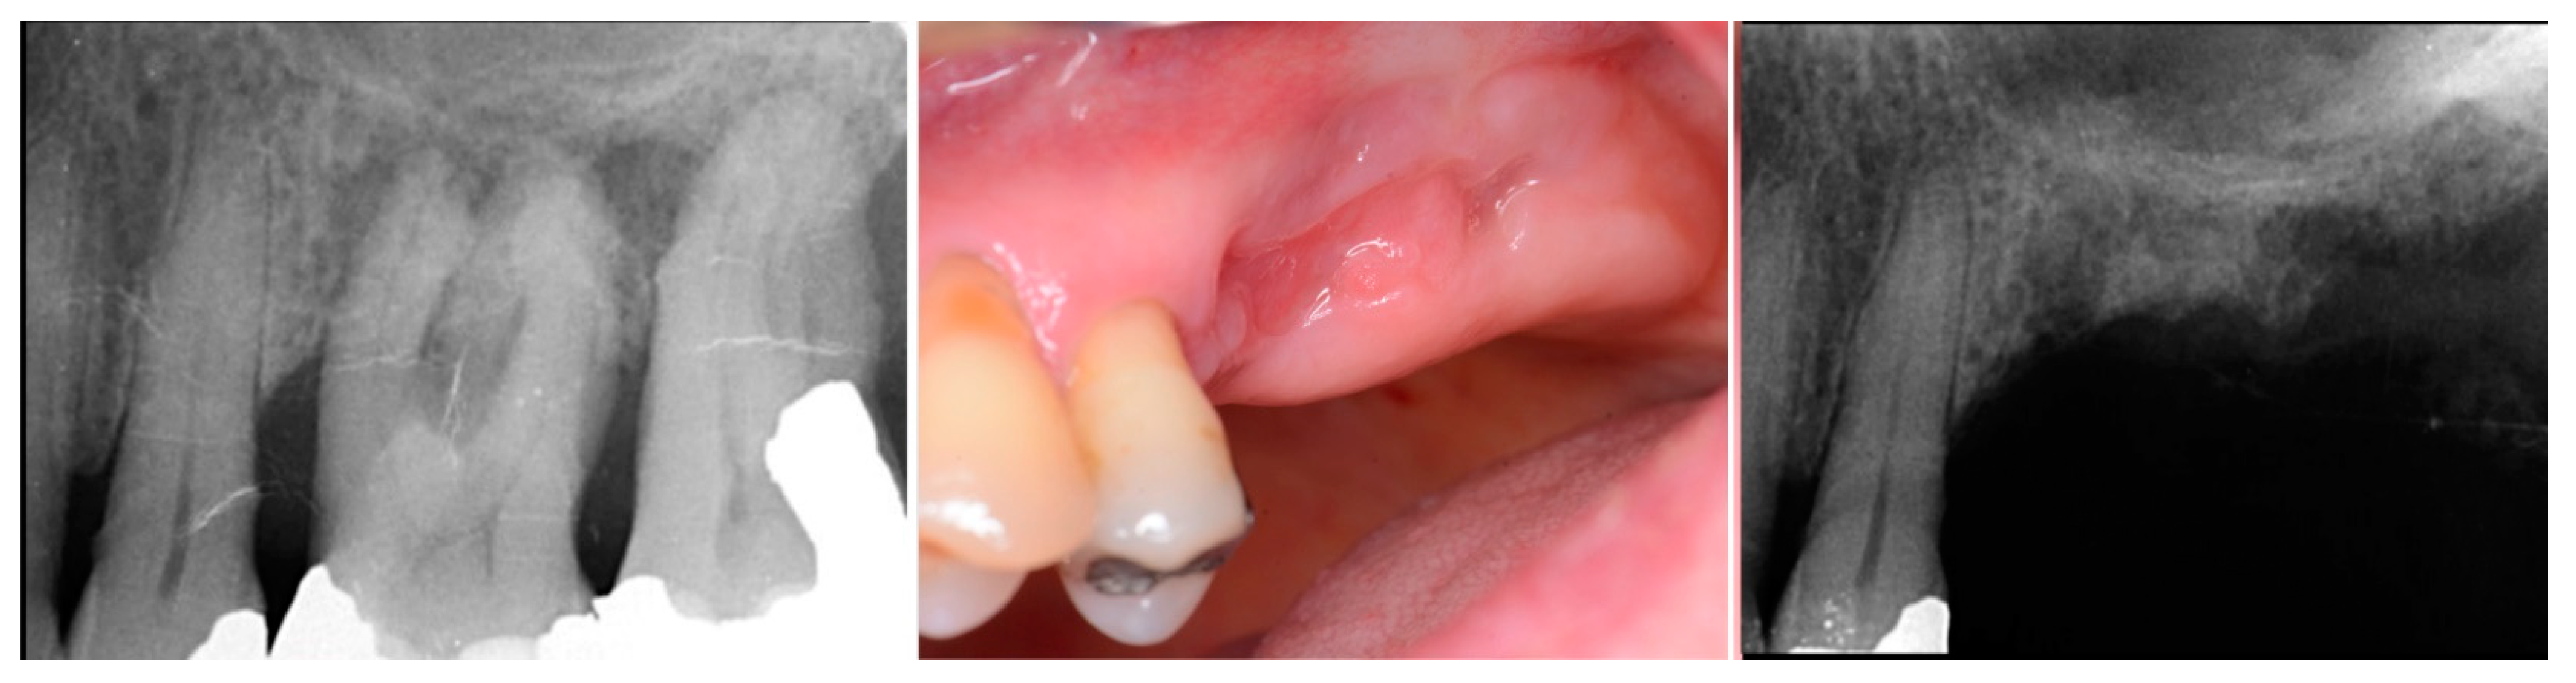

Figure 8.

Failing 1st and 2nd molars related to periodontal bone loss (left), the site following 10 weeks of healing to allow soft tissue closure over the ridge (middle) and a radiograph demonstrating the available bone between the crest and sinus for implant placement (right).

At 10 weeks post-extraction, the patient presented, and consent forms were reviewed and signed for grafting and implant treatment. Soft tissue had healed, closing the site with keratinized tissue (Figure 8, middle). A radiograph was obtained to check what available bone was present at both sites (Figure 8, right). Sufficient height was available to place an implant at the 1st molar site in conjunction with a crestal sinus augmentation, but insufficient height was present at the 2nd molar site which would require grafting to increase crestal height and later implant placement could be performed at that site.